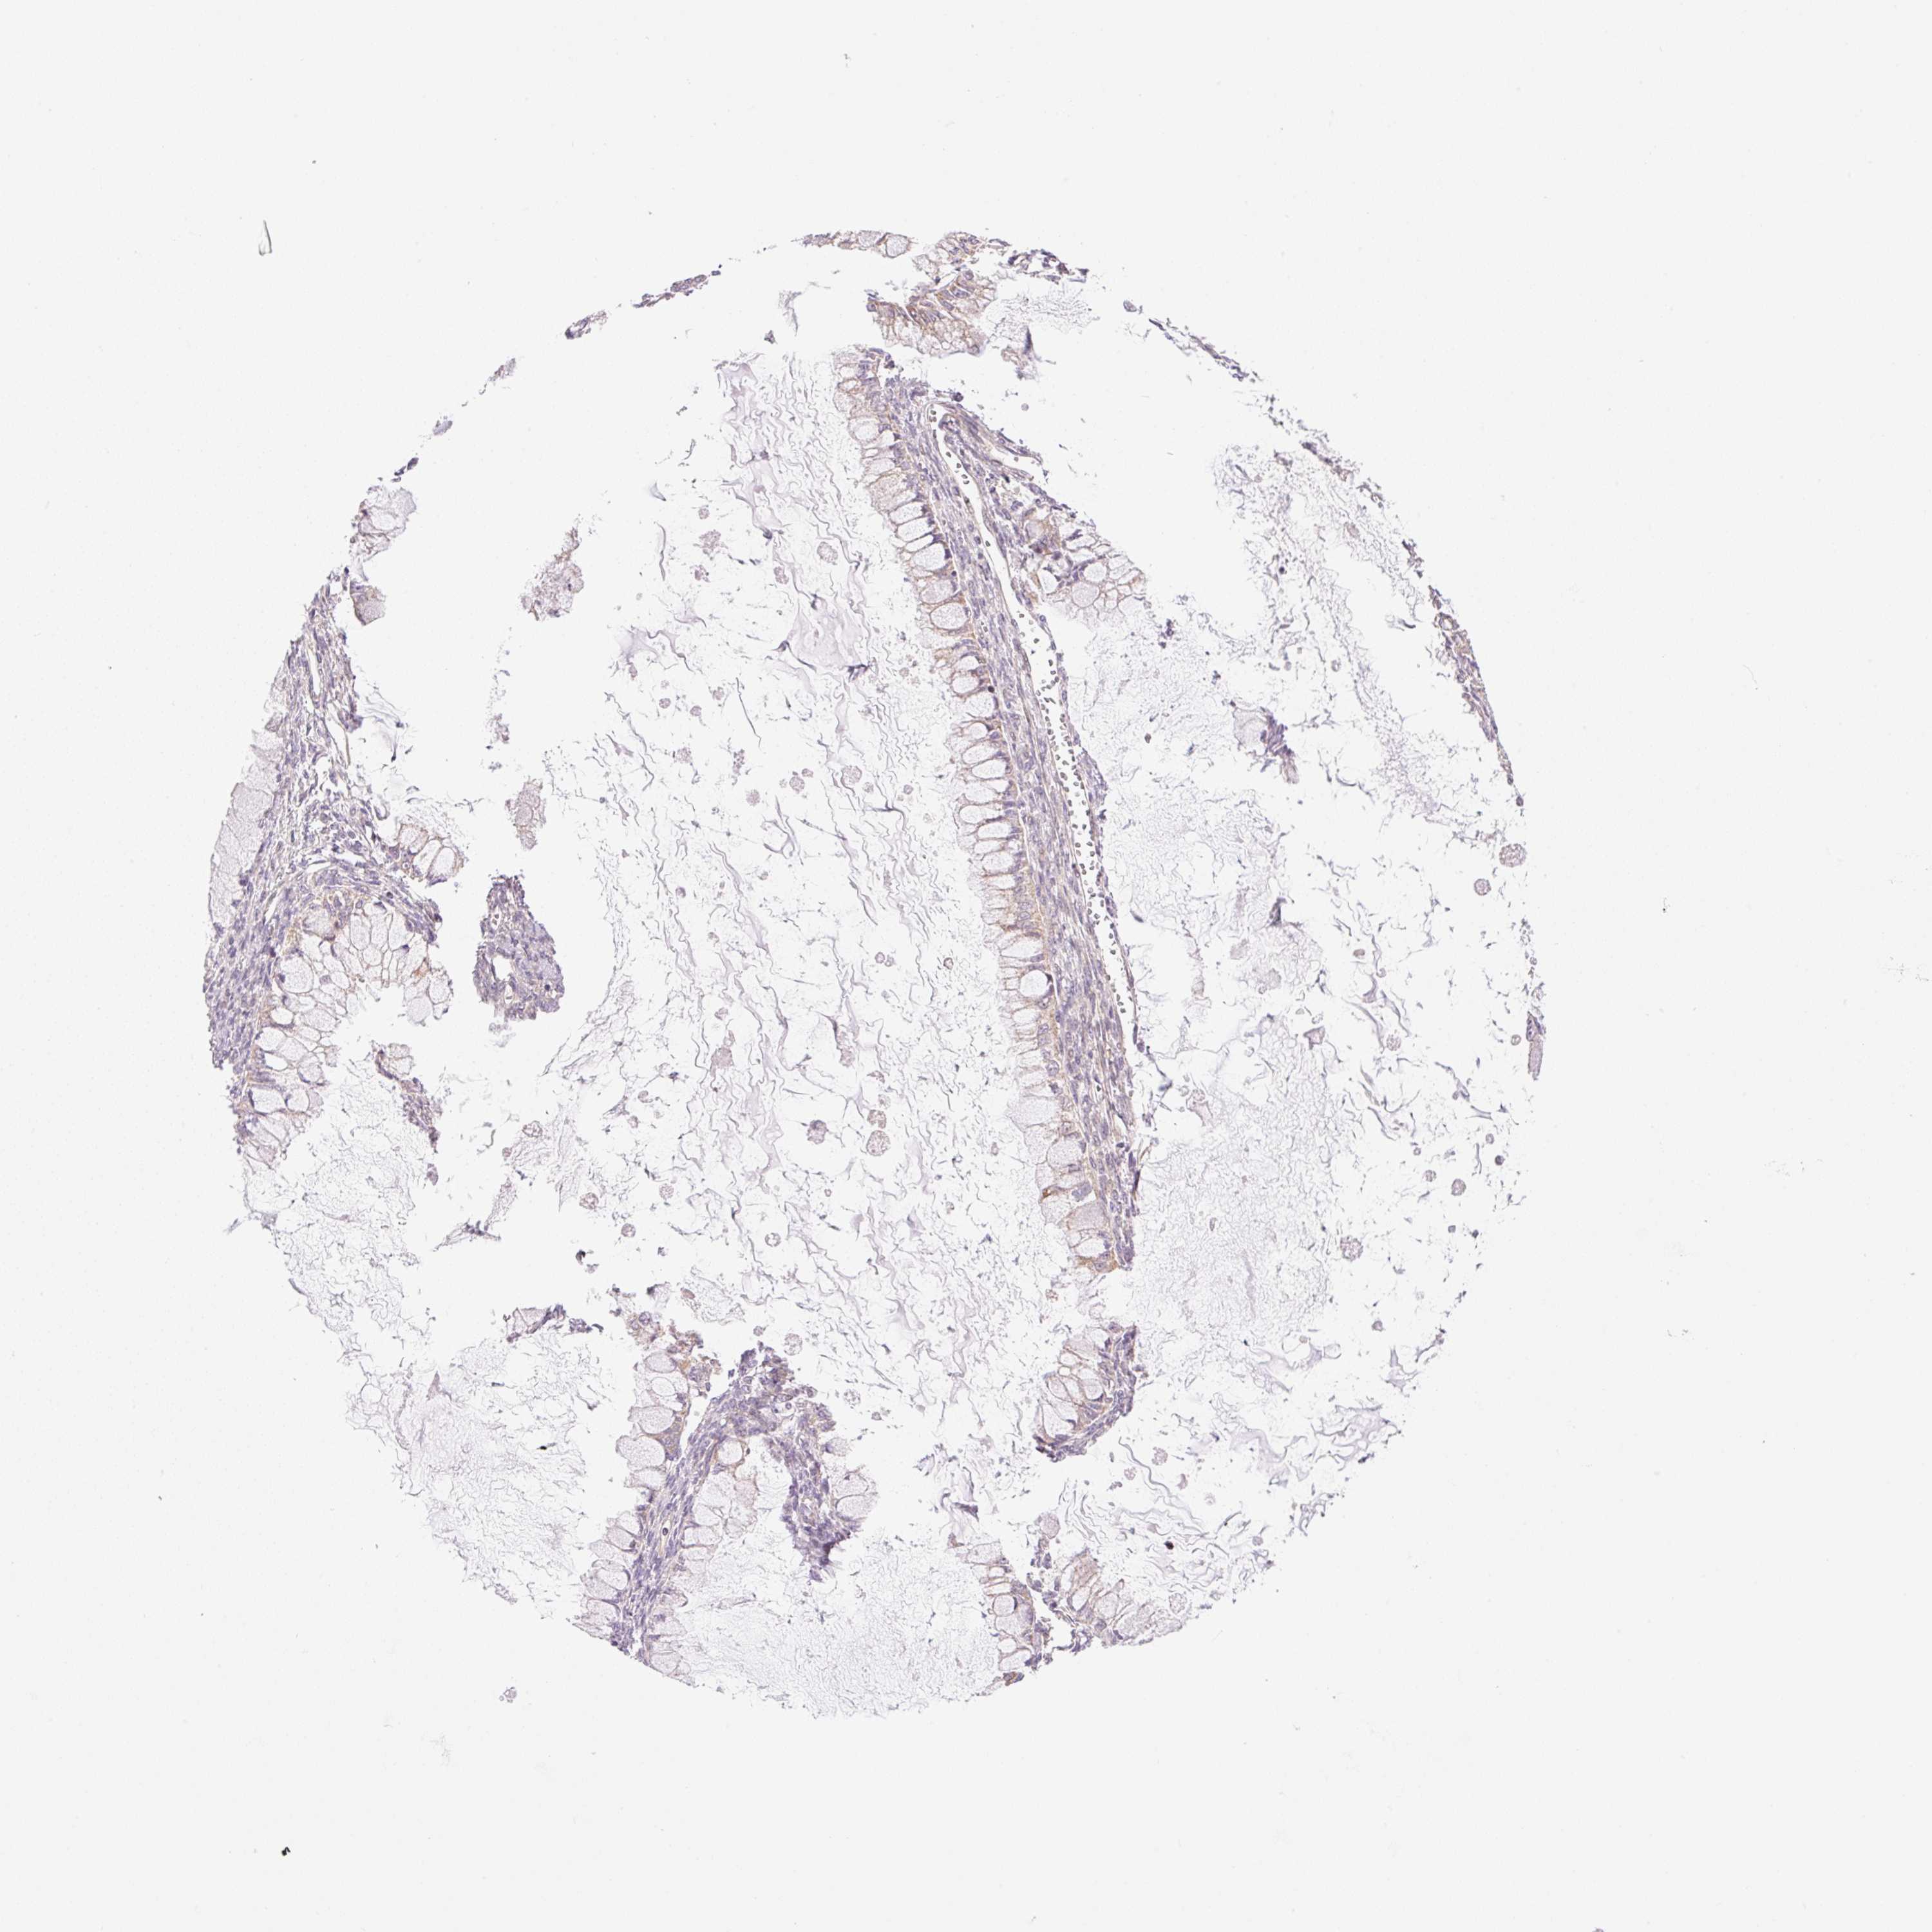

OVARIAN CANCER - Protein expressioni

A mouse-over function shows sample information and annotation data. Click on an image to view it in a full screen mode. Samples can be filtered based on level of antibody staining by selecting one or several of the following categories: high, medium, low and not detected. The assay and annotation is described here.

Note that samples used for immunohistochemistry by the Human Protein Atlas do not correspond to samples in the TCGA dataset.

Antibody stainingi

Antibody staining in the annotated cell types in the current human tissue is reported as not detected, low, medium, or high, based on conventional immunohistochemistry profiling in selected tissues. This score is based on the combination of the staining intensity and fraction of stained cells.

Each image is clickable and will lead to virtual microscopy that enables deeper exploration of all samples and also displays staining intensity scores, fraction scores and subcellular localization as well as patient and tissue information for each sample.

Antibody HPA054639

Cystadenocarcinoma, mucinous, NOS